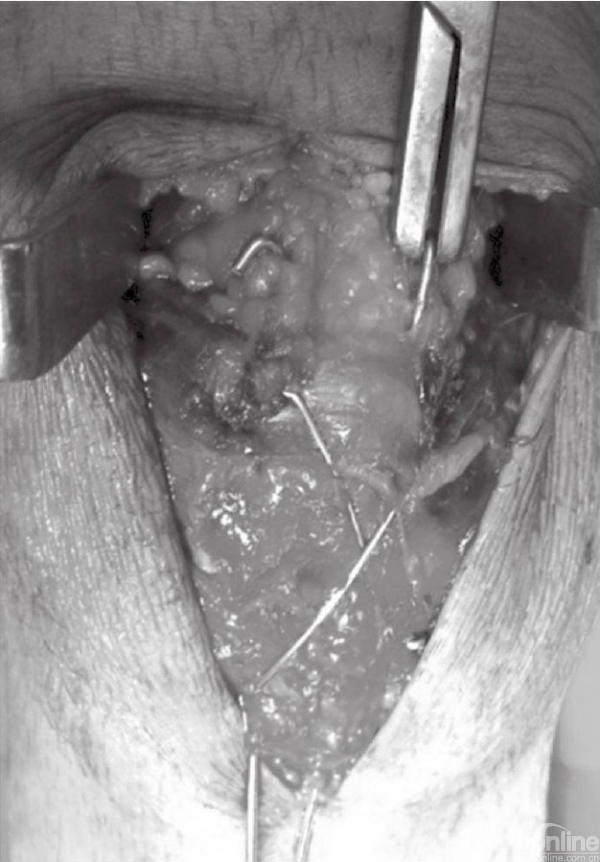

钢缆以“8”字形的方式穿行于髌骨上方。钢缆的一端应留长并做一圆圈,另一端在近髌骨下极处穿过髌韧带(图12)。用捆绑器将钢缆两端系紧。同时收紧髌骨两极的钢丝圈,这可以用钢丝钳或者简单的钳夹完成。钢丝收紧时注意先拉后收紧,这可以防止钢丝重叠,并提供良好的张力。同时收紧可提供两点张力和统一的收紧效果(图13和图14)。钢丝拉紧直至关节边缘微微开启。在膝关节屈曲时该间隙闭合,并在骨折面提供均匀的压力。张力带不应过分紧张,张力过大可导致骨折移位。此时,屈曲膝关节,观察内固定的稳定性以及骨折端的情况。

图12 钢缆末端做“8”字形,在近髌骨下极处穿过髌韧带